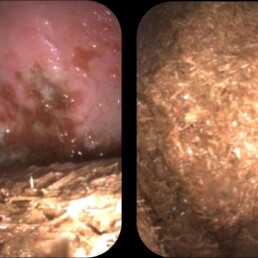

Weiterführende Untersuchungen: Endoskopie

- verminderte Magenentleerung trotz 12h Nahrungskarenz

- erneute Gastroskopie nach insgesamt 24h Hungerphase

- weiterhin Futterball im Magen vorhanden

- Magenschleimhaut nur teilweise beurteilbar

- hochgradige Magengeschwüre in Drüsenschleimhaut sichtbar